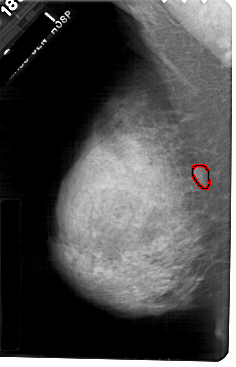

A_1678_1.LEFT_MLO

LEFT_MLO LINES 5491 PIXELS_PER_LINE 3526 BITS_PER_PIXEL 12 RESOLUTION 43.5 OVERLAY

FILE: A_1678_1.LEFT_MLO.OVERLAY

TOTAL_ABNORMALITIES 1

ABNORMALITY 1

LESION_TYPE MASS SHAPE ROUND MARGINS ILL_DEFINED

ASSESSMENT 4

SUBTLETY 3

PATHOLOGY MALIGNANT

TOTAL_OUTLINES 1

BOUNDARY